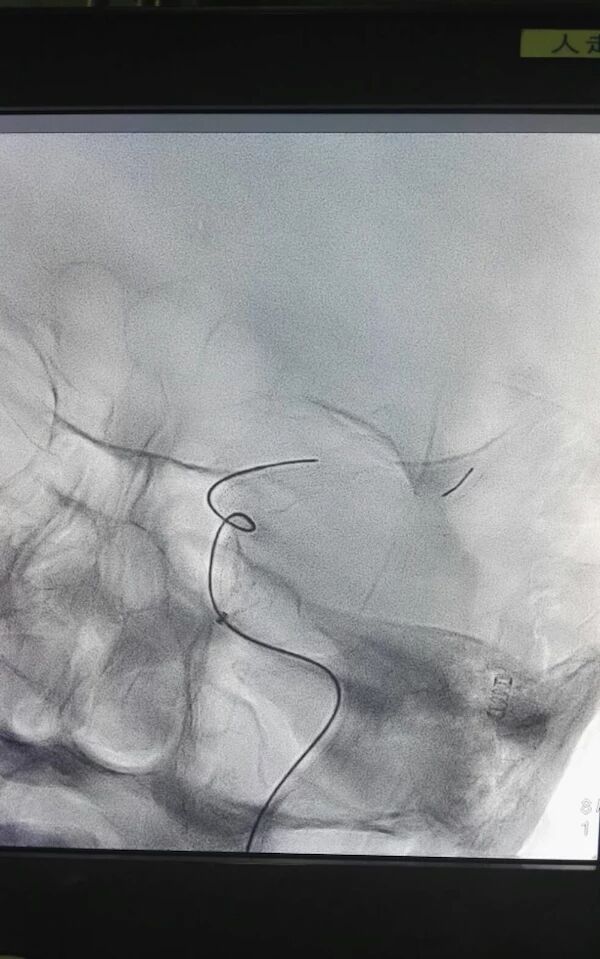

术中用微导管将支架放置狭窄部位,术中见支架Mark显影良好,释放支架5分钟,回收支架,可见支架上附着血栓。